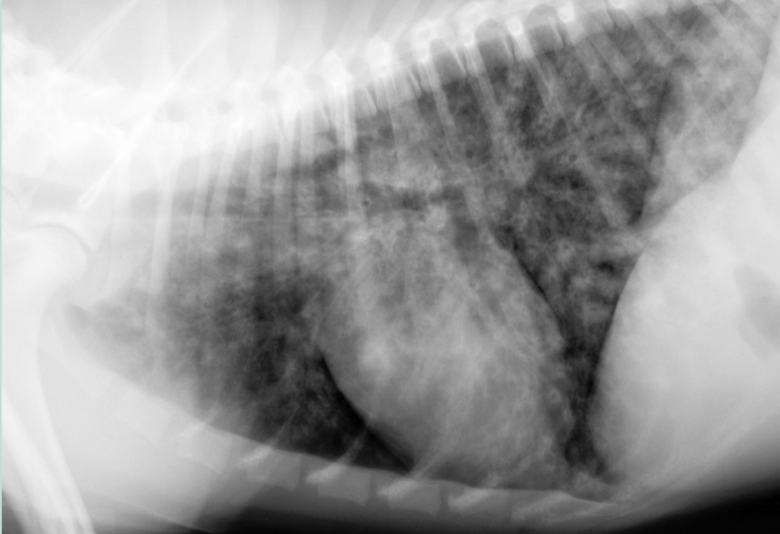

Ted is a 4 mth old Lab Retriever who ran away for 3 hours - he came home panting but not dyspneic. Later in the evening owners notice he is still panting and seems to be struggling for breath

Pattern?

ddx?

Marked interstitial coalescing to alveolar pulmonary pattern of the caudal dorsal lung parenchyma

ddx: non-cardiogenic pulmonary edema, hemorrhage